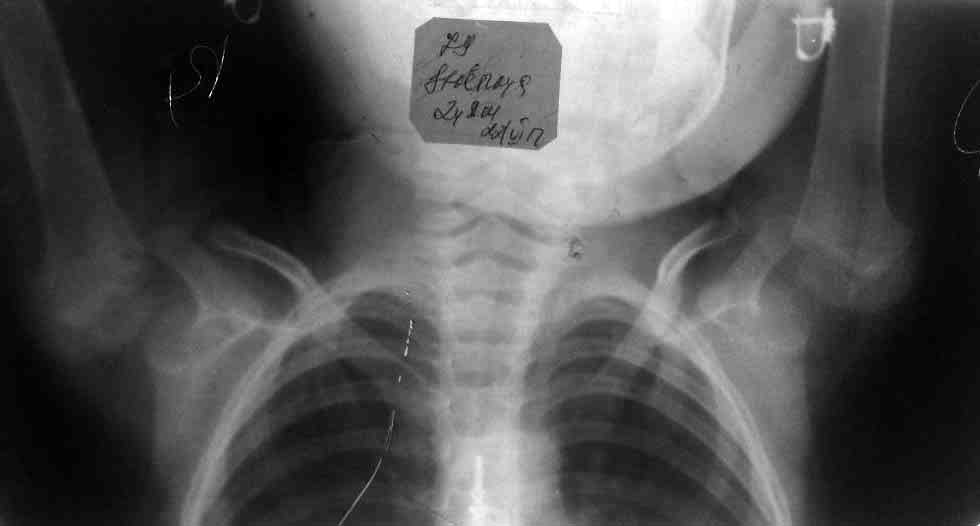

вот рентгеннограмма и фото больной

Соматически ребенок здоров, жалоба матери ребенка на это образование при подъеме рук. С ее слов это образование заметила год назад. Телосложение, кожные покровы, развитие подкожной клетчатки мускулатуры, форма грудной клетки, позвоночник, стояние лопаток, талия поясницы, и прочее без видимой патологии. Пассивное подънятие рук безболезненно, амплитуда движений полная. при активном продънятии рук и пальпации просисходит безболезненное вывыхивание головки плеча вниз с характернным щелчком, самовправлени также безболезненное, то самое образование это головка плеча, на 1-м обзорном снимке взаимоотношения в суставе не нарушены на 2-м с поднятыми руками полная латеропозиция головки плеча от суставной впадины, головка направлена вниз, снимки пришлю чуть позже. пока назначил консервативное лечение так как движения не нарушены, ЛФК, массаж, электростимулятию и электрофорез с прозерином на область плечегого сустава

На представленных снимках рентгенограмм крайне трудно что-то рассмотреть, но угадывается гипоплазия суставной впадины лопатки, что по-видимому и является причиной нестабильности в плечевом суставе.